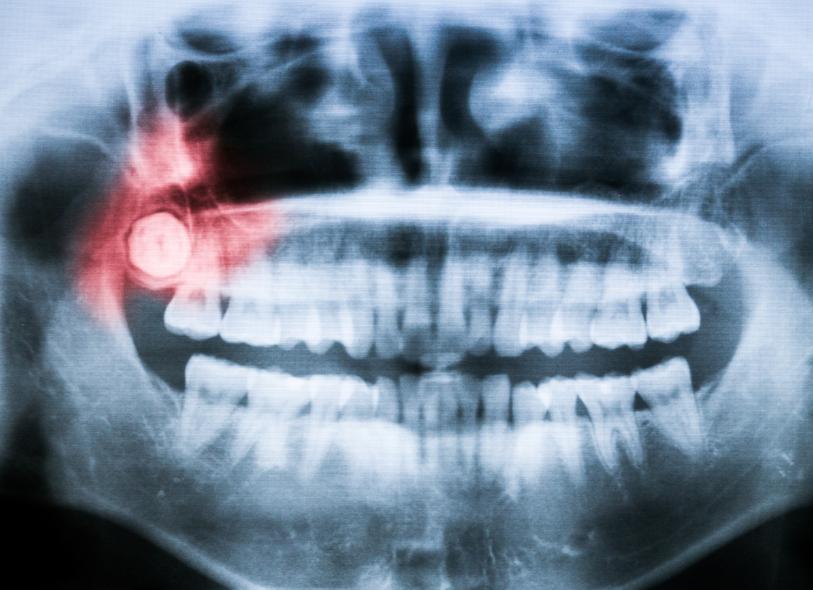

Si sientes dolor y molestias en la zona de las cordales, lo más conveniente es acudir a un odontólogo. El especialista tocará tus encías y posiblemente realizará una radiografía para monitorear su crecimiento y si existe espacio en la boca para ellas. En el caso de que no lo haya, que estén creciendo torcidas o que exista una infección, las mismas deberán ser extraídas por un cirujano maxilofacial mediante una pequeña intervención, con el fin de evitar que muevan el resto de los dientes afectando la mordida del paciente y causando problemas mayores, como infección en más partes de la boca e incluso en el hueso.